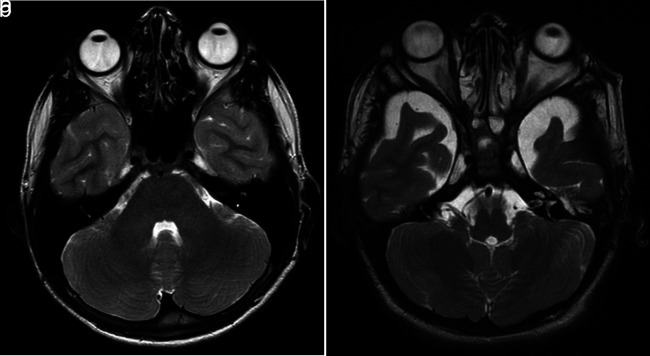

虽然有临床眼科表现的报道,但没有研究记录粘多糖病(MPS) VI型的磁共振成像(MRI)表现。本研究的目的是回顾性确定儿科年龄组粘多糖病(MPS) VI型的眼科影像学表现。方法由两名儿科放射科医生独立评估10例MPS VI型患者和49名健康儿童的脑mri,评估其眼眶体积、眼壁厚度和视神经鞘直径。各组的测量均数采用独立t检验进行比较。通过类内相关系数(ICC)评估评论者之间的一致性和偏倚。结果共59例患儿[女孩32例(54.23%),男孩27例(45.77%);年龄范围4-16岁;平均年龄(10.37±3.73岁)。统计分析显示,MPS VI型患者眼球较小,眼壁较厚(P < 0.001和P < 0.001)。两组视神经鞘直径比较差异无统计学意义(P=.648)。结论与健康儿童相比,MPS VI型患者眼球体积减小,眼壁厚度增加。因此,我们建议眼科影像学结果可能被证明是诊断MPS患者的辅助工具。

PURPOSE lthough clinical ophthalmologic findings have been reported, no study documented magnetic resonance imaging (MRI) findings in mucopolysaccharidosis (MPS) type VI. The aim of this study was to determine the ophthalmologic imaging findings of MPS type VI in the pediatric age group retrospectively. METHODS Brain MRIs of 10 patients with MPS type VI and 49 healthy children were evaluated independently by two pediatric radiologists for the following characteristics: globe volume, ocular wall thickness, and optic nerve sheath diameter for each orbit. The means of the measurement of each group were compared by using an independent t-test. Agreement and bias between reviewers were assessed by intra-class correlation coefficients (ICC). RESULTS A total of 59 children [32 girls (54.23%), 27 boys (45.77%); age range, 4-16 years; mean age, 10.37 ± 3.73 years] were included in the study. Statistical analysis revealed smaller eyeballs and thicker ocular walls of patients with MPS type VI (P < .001 and P < .001, respectively). However, there was no statistically significant difference in terms of optic nerve sheath diameter between the two groups (P=.648). CONCLUSION Patients with MPS type VI displayed reduced globe volumes and increased ocular wall thicknesses compared to the healthy children. Therefore, we recommend that ophthalmologic imaging findings might prove to be an auxiliary tool in the diagnosis of MPS patients.